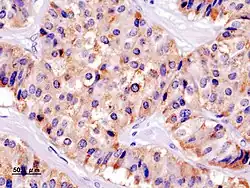

Cytoplazma beta buněk obsahuje granula (beta-granula), která mají na rozdíl od granulí alfa buněk proměnlivou velikost a tvar (průměrně 0,2 μm). Pro pozorování pod světelným mikroskopem se obarvují chromovým hematoxylinem, aldehydovým fuchsinem či thioninem. V histologických preparátech jsou beta buňky světlejší oproti alfa buňkám, protože obsah beta buněk se extrahuje alkoholem.

Mitochondrie beta buněk jsou v porovnání s alfa buňkami větší, B-buňky mají zřetelnější Golgiho aparát a endoplazmatické retikulum. V elektronovém mikroskopu je vidět nápadné prosvětlení pod obalující membránou. Granula B buněk nemají jednotnou strukturu, mohou být homogenní i zrnitá a mají světlou matrix, ve které lze najít jedno i více malých krystaloidních tělísek.[1][2]